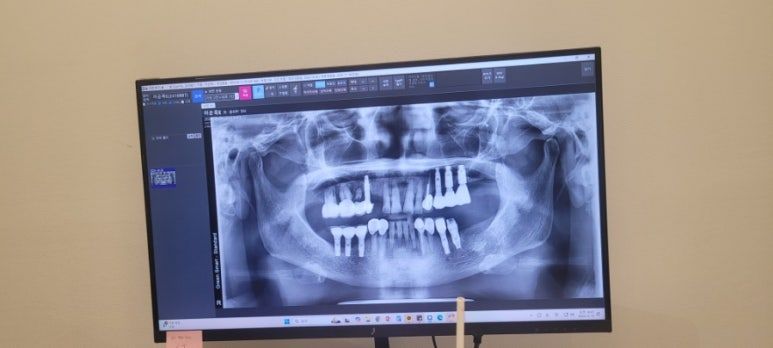

이번 임플란트 치료 끝나면 약 15년 유지 가능하고 5년은 보증기간이란다

계속적으로 청결과 건강유지시 20년 사용도 가능하다고 하니 치료 잘 받으시고 나면 이빨 걱정을 없으리라 생각되었다.

이렇게 전체 브리핑을 듣고 선금 결제를 하고 오늘 진료 일정에 대해 들었다.

오늘 아빠는 6개 식립하고 엄마는 4개 식립하신다고 한다.